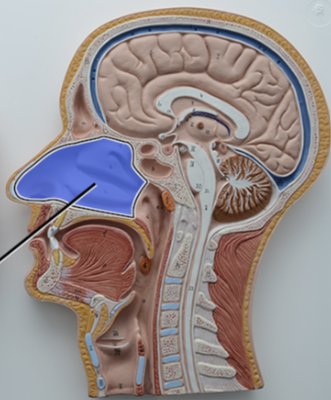

What structure is this?

Diaphragm

What structure is this?

Hard Palate

What structure is this?

Soft Palate

What structure is this?

Uvula

What structure is this?

Nasal cavity

What structure is this?

Superior Nasal Concha

What structure is this?

Middle Nasal Concha

What structure is this?

Inferior Nasal Concha

What structure is this?

The nasopharynx region of the pharynx

What structure is this?

The Oropharynx region of the pharynx

What structure is this?

The Laryngopharynx region of the pharynx

Nasal Septum